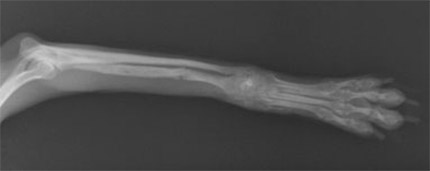

前肢橈尺骨骨折

1kg〜4kgの超小型犬が、室内でソファや抱っこの状態から飛び降りるくらいのことで骨折する場合が多いです。特に人気犬種のTプードルやチワワなどに多く認められます。

手術前

手術後

1.6kgのトイプードルの橈尺骨骨折です。プレートおよびスクリューを用いて固定、治療しました。